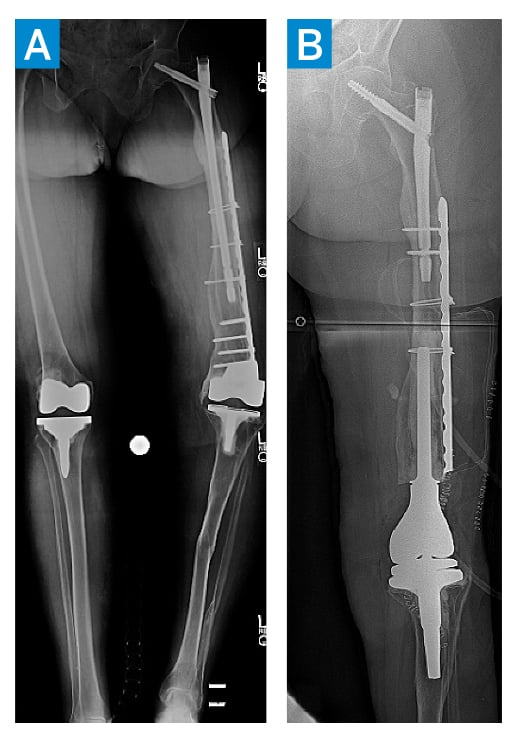

A 75-year-old woman presented with mechanical loosening of a left knee arthroplasty. She had a history of tibial and femoral fractures to the left leg with a retained cephalomedullary nail, lateral femoral plate, and post-traumatic tibial deformities (Figure 1A). She underwent a complex left knee revision surgery, with exchange of the cephalomedullary nail to a shorter construct, cutting of the lateral plate, and conversion to a distal femoral replacement (Figure 1B).

Figure 1: Anteroposterior views of bilateral legs on initial presentation (A) followed by complex left knee revision with nail exchange, partial plate removal, and distal femoral implantation (B).